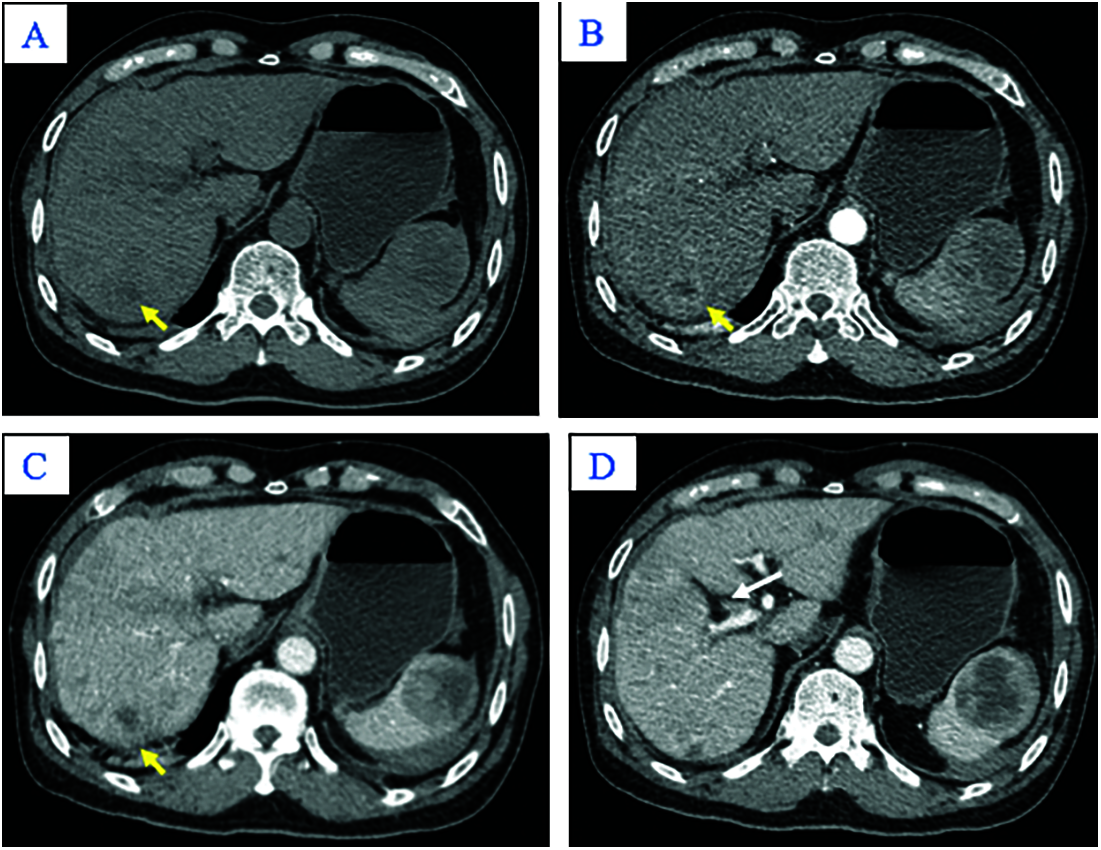

A 65-year-old man was admitted to our hospital complaining of fatigue and mild left-side abdominal pain without any history of recent trauma. He had a history of chronic hepatitis B infection for the past 6 years. Physical examination revealed a palpable mass below the left costal margin, which was defined as an enlarged spleen on abdominal ultrasound. Additionally, multiple nodules and masses were detected in the spleen and liver on ultrasonography. The patient was transferred to the oncology department with suspicion of metastatic disease with an unknown primary. Two days after admission, the patient developed severe acute abdominal pain, hypotension (80/50 mmHg), and tachycardia (105 beats per minute). Laboratory tests revealed a low hemoglobin (85 mg/dL), elevated alpha-fetoprotein (AFP; 8757 ng/mL), and elevated protein induced by vitamin K antagonist II (PIVKA-II; 23043.11 AU/mL). Bedside ultrasonography detected free intraperitoneal fluid with mixed internal echogenicity, suggesting hemoperitoneum. Therefore, urgent CECT was performed, which revealed a large quantity of hyperdense, free fluid in the pelvis and surrounding the inferior splenic pole, most consistent with hemoperitoneum (Fig. 1A). Multiple splenic masses were observed, with the largest in the inferior pole measuring 6 x 6 cm. The masses were hypodense on pre-contrast images (Fig. 1A) and demonstrated mild heterogeneous enhancement in the arterial phase (Fig. 1B), without gross change on portal venous (Fig. 1C) or delayed phase images (Fig. 1D). Discontinuity of the splenic capsule consistent with tumor laceration, was observed on post-contrast images without signs of active bleeding (Figs. 1C and 1D). In addition, multiple hepatic masses were observed, which were hypodense on pre-contrast images, and demonstrated marked peripheral hyperenhancement in the arterial phase, and non-peripheral washout in the portal venous and delayed phase images (Figs. 2A–2C). Right anterior portal vein thrombosis (Fig. 2D) was also identified. Multiple enlarged lymph nodes were observed in the hepatic hilum and paraaortic space, in addition to osteolytic lesions in the fourth and eighth thoracic vertebral bodies. The patient was diagnosed with hemoperitoneum due to presumed ruptured splenic metastasis, and an emergency splenectomy was performed. A liter of blood in the abdomen and a lacerated splenic mass were found on surgical exploration. Histopathology revealed a solid tumor with a well-defined margin between the tumor and the splenic parenchyma (Fig. 3A). The tumor cells were arranged in a trabecular pattern, with prominent nucleoli and hyperchromatism (Fig. 3B). Immunohistochemically, the neoplastic cells revealed solid and diffuse positivity for the hepatic marker hepatocyte paraffin 1 (HEPAR-1), indicating an HCC origin (Fig. 3C). The patient was diagnosed with Grade 2 HCC, with splenic and bone metastases, and metastatic abdominal lymphadenopathy. The patient was treated with targeted therapy. Finally, this patient was lost to follow-up.

Figure 3: Hematoxylin and eosin staining (A and B). (A) The tumor was solid, with a well-defined margin between the lesion and the splenic parenchyma (arrow; × 40). (B) The tumor cells were arranged in a trabecular pattern, with prominent nucleoli and hyperchromatism (×400). (C) Immunohistochemistry results (×100) showed tumor cells positive for the hepatic marker HEPAR–1